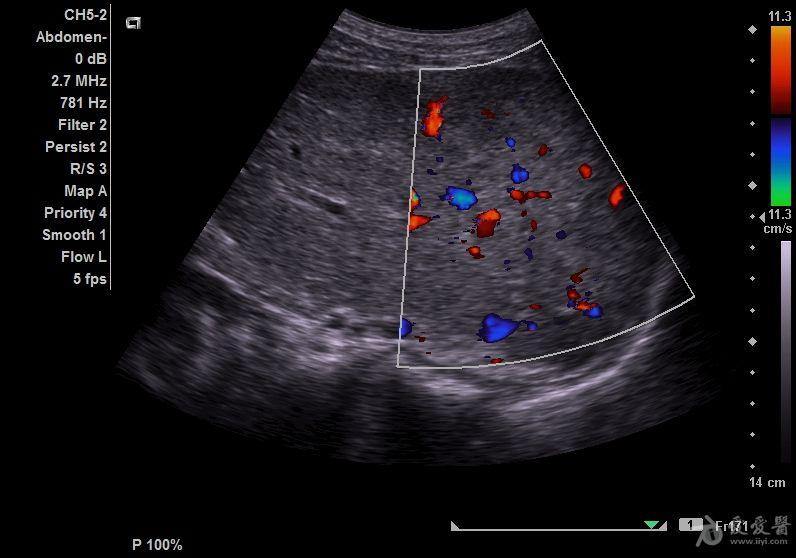

弥漫性肝癌超声图片

弥漫性肝癌超声图片,弥漫性肝癌图片

经典的转移性肝癌合并腹水(病理提示直肠腺癌) - 超声

考虑转移性肝癌 - 超声医学讨论版 - 爱爱医医学论坛